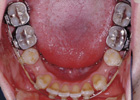

歯を抜いて治療した例 その1

治療途中